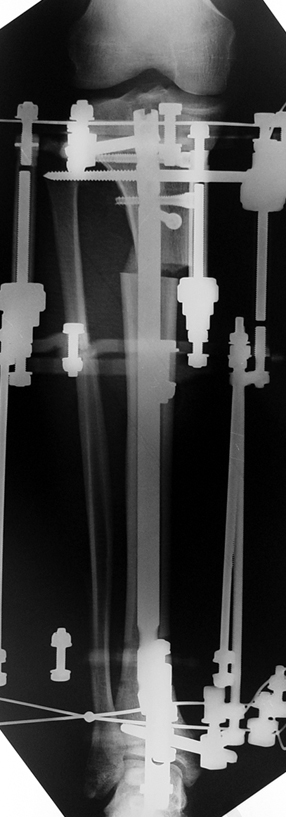

The application of the external fixator: Three Schanz screws are placed distally and three screws are placed proximally. At least 1 mm of distance shall remain between the screws and the nail.

In selected cases, we prefer to use a combination of a unilateral dynamic axial fixator and an interlocked intramedullary nail, in order to protect the length and alignment after the completion of the lengthening procedure. As a prerequisite for this technique, the narowest diameter of the medullary cavity shall be wider than 7 mm and the length of the nail segment distal to the osteotomy site shall be at least 8 cm. after the completion of the lengthening procedure.The intramedullary nail neutralizes shear and bending forces on femur during lengthening, shortens external fixation time, and protects newly formed bone against fractures. In our series, subtrochanteric osteotomy was performed in one case. No varus angulation occured despite the intramedullary nail.

Ilizarov stressed the significance of endosteal blood circulation for distraction osteogenesis. Although we placed the intramedullary nail after reaming the femur in all cases, the time for callus formation was not longer than expected. Thus we found that there is no slowing in the rate of new bone formation due to disruption of medullary blood flow. The rationale of this finding is revascularization that occurs following reaming of the medullary cavity, the fixation stability with the intramedullary nail and early functional weight bearing. The potential disadvantages of a combined use of external and internal fixation metods are increased blood loss, intramedullary infection, risk of fat embolism and excessive metal load.The most fearsome complication is a deep intramedullary infection (panosteomyelitis) triggered by pin tract infection.No such complication was encountered in our series. In order to avoid this complication, after the completion of lengthening the nail shaill be interlocked from the medial side, and contact of internal and external fixator pins shall be avoided.